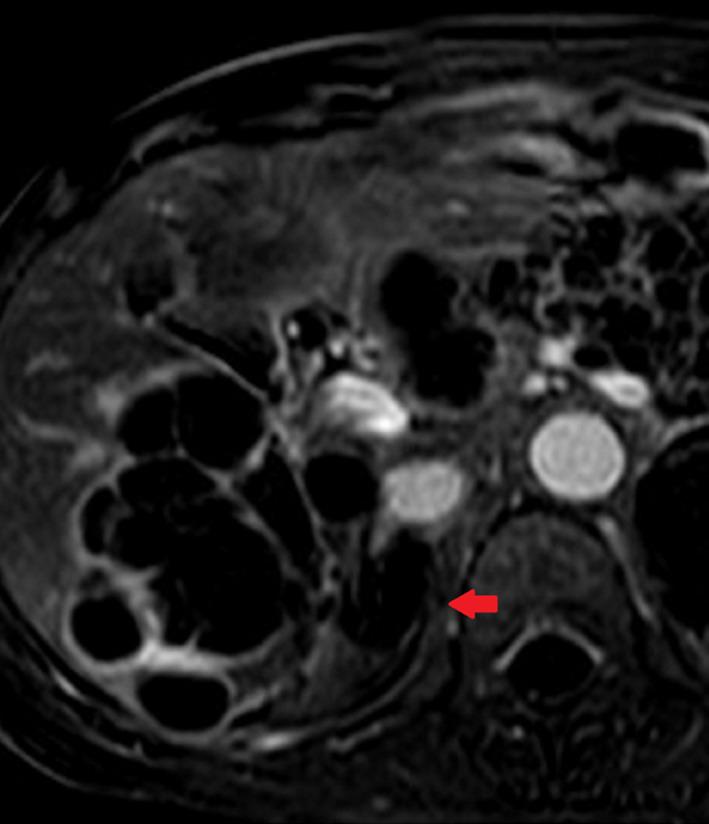

Adrenal pheochromocytoma treated by combination of adrenal arterial embolization and radiofrequency ablation.

Combined therapy with adrenal arterial embolization and RF ablation may represent a useful therapeutic option with curative properties in select patients with pheochromocytoma.